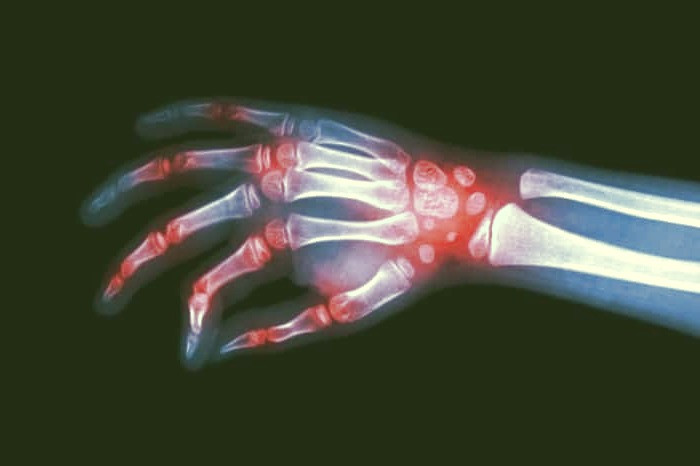

عوارض و درمان های بیماری آرتریت روماتوئید

آرتریت روماتوئید یک اختلال مزمن و پیشرونده است که با علائم شدیدی از درد، سوزش و ورم مفاصل همراه است. این بیماری خودایمنی در صورت عدم درمان مناسب، منجر به تغییر و تحول در ساختار طبیعی مفاصل و استخوان ها خواهد شد. به طور کلی، آرتریت روماتوئید یک شرایط بالینی پیچیده است که نیازمند مدیریت دقیق و درمان به موقع توسط متخصصان مربوطه می باشد تا از پیشرفت و تشدید علائم آن جلوگیری شود.

رماتوئید آرتریت یک اختلال التهابی مزمن است که بر مفاصل شما تأثیر می گذارد. در برخی افراد، رماتوئید آرتریت می تواند طیف وسیعی از سیستم های بدن از جمله پوست، چشم، ریه، قلب و عروق خونی را تحت تأثیر قرار دهد. رماتوئید آرتریت یک اختلال خودایمنی است و زمانی رخ می دهد که سیستم ایمنی شما به اشتباه به بافت های بدن خود حمله می کند. این بیماری می تواند باعث درد، تورم و سفتی مفاصل شود و در نهایت به آسیب دائمی مفاصل منجر شود. عوامل ژنتیکی، محیطی و هورمونی در ایجاد این بیماری نقش دارند.

آرتریت روماتوئید برعکس پوکی استخوان ، روی خطوط مفصلی تاثیر می گذارد و ورم دردناکی را ایجاد می کند که در نهایت منجر به تغییر شکل مفصل در استخوان خواهد شد . این التهاب که مربوط به آرتریت روماتوئید می باشد ، می تواند به دیگر بخش های بدن شما نیز آسیب وارد کند.

آرتریت روماتوئید زمانی اتفاق می افتد که سیستم ایمنی شما به خط غشایی در اطراف مفاصل بدن خودتان حمله می کند . نتیجه آن ضخیم شدن این خط بافت غشایی می شود که در نهایت باعث آسیب به غضروف و استخوان داخل مفصل می گردد.

تاندون ها و رباط هایی که مفصل ها را در کنار یکدیگر نگه می دارند ، در لین شرایط کش آمده و ضعیف می شوند . به تددیج مفصل شکل و حالت اصلی خود را از دست می دهد.

آرتریت روماتوئید تشخیص سختی دارد ؛ مخصوصا اگر بیمار در مراحل اولیه باشد . البته پزشکان معاینه فیزیکی انجام می دهند تا وضعیت ورم ، مفصل ها ، قرمزی و گرمای آن ها را بررسی کند . همچنین رفلاکس ها و قدرت عضلانی را در نظر می گیرد.

عکس برداری :